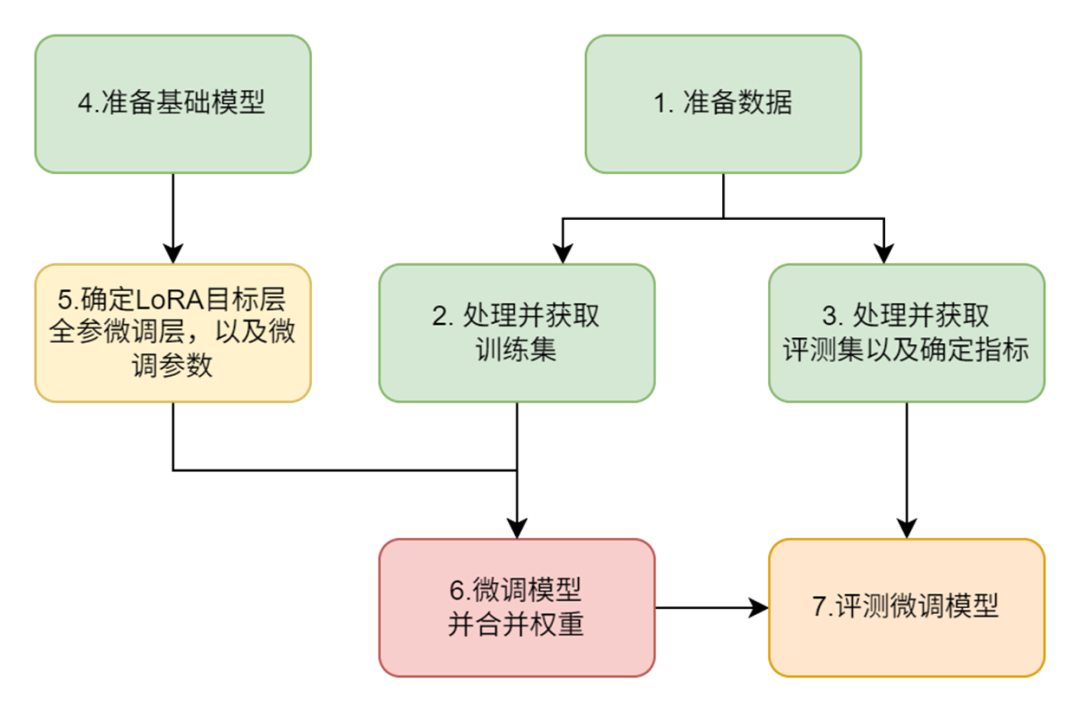

整体微调步骤如下:

第一步:准备「医学教材」—— 数据集

第二步:给问题加个「模板滤镜」—— 数据处理

为了测评微调后的模型效果,我们需要将数据集切分为训练集和测试集并保存,切分比例为9:1。

第三步:给模型定制「训练计划」—— 微调模型

上面代码中,使用LazyLLM的TrainableModule来实现:微调->部署->推理:

⚒️模型配置:

model_path指定了我们要微调的模型,这里我们用Internlm2-Chat-7B,直接指定其所在路径即可;

⚒️微调配置:

-

.mode设置了启动微调模式finetune;

-

.trainset 设置了训练用的数据集路径;

-

.finetune_method 设置了用哪个微调框架及其参数,这里传入了一个元组(只能设置两个元素):

➡️第一个元素指定了使用的微调框架是Llama-Factory:finetune.llamafactory

➡️第二个元素是一个字典,包含了对该微调框架的参数配置

⚒️推理配置:

- .prompt 设置了推理时候用的Prompt,注意,这里为了和微调的Prompt中的system字段保持一致,所以开启drop_builtin_system以将原system-prompt给替换为`You are a helpful assistant.`;

- .deploy_method 设置了部署用的推理框架,这里指定了vLLM这个推理框架。

⚒️评测配置:

这里通过.evalset来配置评测集;

⚒️启动任务:

.update 触发任务的开始:模型先进行微调,微调完成后模型会部署起来,部署好后会自动使用评测集全部都过一遍推理以获得结果。

微调loss曲线:

第四步:「成果验收」检实力 —— 效果评测